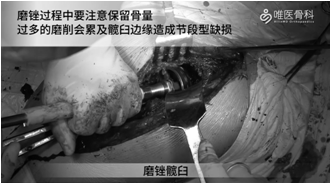

髋臼制备:磨锉髋臼,磨锉过程中要注意保留骨量,过多的磨削会累及髋臼边缘造成节段型缺损。本病例起初用65mm髋臼锉测试稳定性不佳,然后使用67mm髋臼锉,边磨锉边观察其与宿主骨的关系,然后进行反锉压实。测试髋臼锉稳定性好,如果仍怀疑其稳定性,可使用髋臼假体试模再次评估其稳定性。